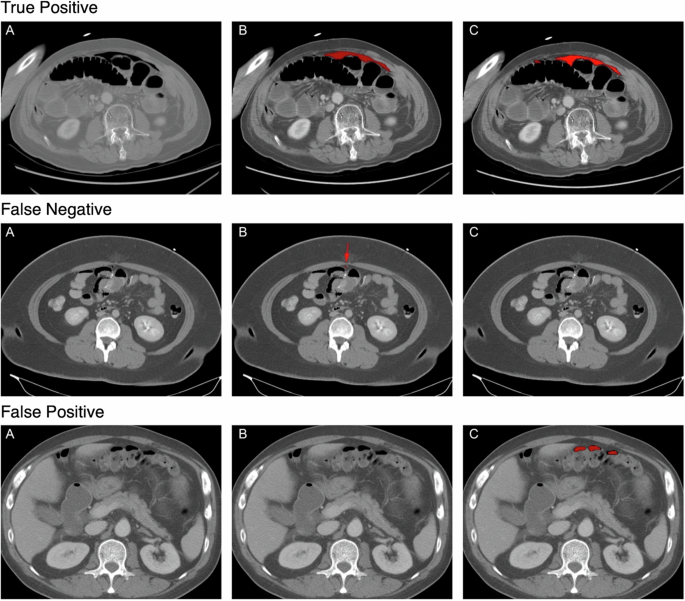

For each scenario: (A) represents the original CT scan image, (B) denotes the ground truth labeling, and (C) illustrates the mask generated by the trained segmentation model.

The missed cases in both the simulated and prospective test sets highlight an important aspect of the model’s performance in real-world settings. Upon reviewing the cases that PACT-3D failed to predict, we found that most missed instances involved free air that was scattered and appeared in retroperitoneal areas, which can easily be mistaken for other bowel gas at first glance. Specifically, the model may miss cases with smaller air bubbles, but it reliably identifies cases with larger, cumulated volumes of free air, which typically require urgent intervention. On the other hand, the model’s high specificity demonstrates that it won’t easily trigger false alarms, reducing the risk of clinician fatigue. In cases where PACT-3D incorrectly identified pneumoperitoneum, a review of the prediction masks revealed that most errors were due to the model mistakenly identifying air-containing abscesses, subcutaneous emphysema, air within fluid collections, distended bowel gas, or air density artifacts related to artificial implants (Supplementary Table 3). Although these cases were not correctly diagnosed, many still required medical intervention. This selective performance could make PACT-3D a valuable triage tool in emergency and critical care, where the primary goal is to quickly identify and prioritize cases that necessitate immediate surgical intervention.